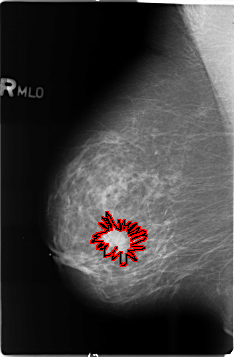

B_3488_1.RIGHT_MLO

FILE: B_3488_1.RIGHT_MLO.OVERLAY

TOTAL_ABNORMALITIES 1

ABNORMALITY 1

LESION_TYPE MASS SHAPE IRREGULAR-ARCHITECTURAL_DISTORTION MARGINS SPICULATED

ASSESSMENT 5

SUBTLETY 5

PATHOLOGY BENIGN

TOTAL_OUTLINES 1

BOUNDARY